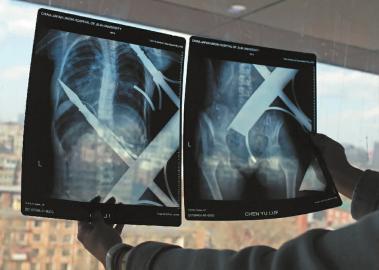

X光片顯示一根鋼筋將小女孩的右側(cè)肩膀刺穿,另外一根則從后背腰部以上靠近脊椎的地方穿入 白石 攝

在急診室的病床上,李紅旭看到了小雨?!八龗熘跗?,意識(shí)比較清醒?!边M(jìn)一步觀察,李紅旭一時(shí)說(shuō)不出話來(lái)———一根鋼筋穿透小雨右側(cè)肩膀,另一根則從后背腰部以上靠近脊椎的地方穿入,從小雨左肩部分穿了出來(lái)。兩根鋼筋由兩根角鐵連接,距離事發(fā),小雨背著這片鐵柵欄已經(jīng)近7個(gè)小時(shí)了。